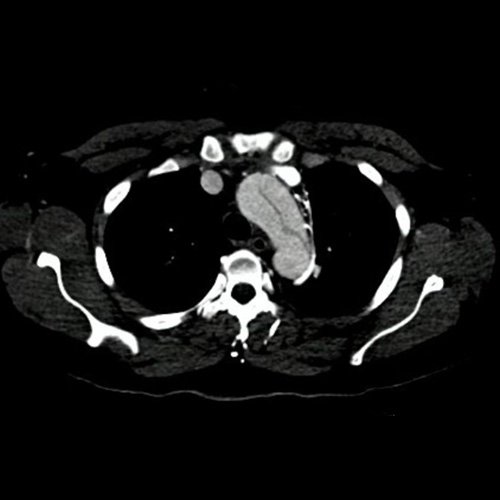

Angiotomografía con contraste endovenoso de cayado aórtico. Corte axial.

• Angio-TCMS de aorta toracoabdominal y vasos iliofemorales - pre informe (día 0): Interpretación: Se identifica un flap de disección aórtica, que se extiende desde la raíz aórtica, hasta el segmento distal de la aorta torácica descendente, asociado a dilatación aneurismática de la raíz aórtica y la aorta ascendente. No se observa disección de aorta abdominal al momento del examen. El flap de disección compromete la aorta ascendente, el arco aórtico y los tres vasos supraaórticos, extendiéndose hacia el tronco braquiocefálico derecho, con compromiso de la arteria subclavia derecha, así como también de la porción proximal de la arteria carótida primitiva izquierda y de la arteria subclavia izquierda. No impresiona compromiso de la emergencia de las arterias coronarias por esta metodología. Diámetros de la Aorta en sus diferentes porciones:  Senos de Valsalva: 40 mm.  Región media de aorta ascendente: 37 mm. Región media del cayado: 23 mm. Región media de la aorta descendente: 22 mm. A nivel de las cruras diafragmáticas: 19 mm. A nivel del origen del tronco celíaco: 18 mm. A nivel infrarrenal: 14 mm. Previo a su bifurcación iliaca: 13 mm. Hipertrofia del ventrículo izquierdo. Derrame pericárdico de 13 mm de espesor a nivel de cara anterior, de densidad promedio de 30 UH. El esófago es de calibre y trayecto normales. El mediastino está en posición central. No se observan adenomegalias mediastinales, axilares o hiliares. El árbol traqueobronquial no presenta alteraciones. Áreas de aneumatosis bibasal. No se observa derrame pleural. El hígado es de forma, tamaño y situación habituales. Su superficie es lisa, y sus bordes son agudos. El parénquima hepático presenta atenuación heterogénea, con áreas hipodensas difusas, hallazgos que podrían estar en relación con trastorno perfusional. Se observa además edema periportal. La vía biliar intra y extrahepática es de calibre conservado. La vesícula biliar es de forma, tamaño y situación normales, sin imágenes que sugieran la presencia de litiasis. Tener en cuenta que este método puede pasar por alto litiasis colesterínicas. Edema perivesicular. El bazo es de forma, tamaño y situación normales. El eje esplenoportal es de calibre y trayecto conservado, permeable. El páncreas es de características normales. El conducto de Wirsung es de calibre conservado. Las glándulas adrenales son normales. Ambos riñones son de forma, tamaño y situación habituales. Concentran y eliminan normalmente la sustancia de contraste, sin evidencia de alteraciones calicopiélicas ni ureterales. La vena cava inferior y las venas ilíacas primitivas, internas, externas y femorales son de calibre y trayecto conservados, permeables. No se observan adenomegalias intraperitoneales, retroperitoneales, ilíacas ni inguinales. No se observan alteraciones a nivel del tracto gastrointestinal. Vejiga con escasa repleción, con sonda balón en su interior. El útero es de forma, tamaño y situación conservada, sin alteraciones densitométricas, en anteversoflexión. En topografía de ambos anexos se observan colecciones líquidas de aspecto funcional que miden 23 mm a izquierda y 18 mm a derecha. Escasa cantidad de líquido libre en el fondo de saco de Douglas. Espondiloartrosis de la columna dorso-lumbar.